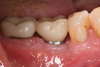

Based on clinical and radiographic examination of the area, the patient was diagnosed with moderate peri-implantitis subcategory A (Figure 10 and Figure 11).19 Pocket depths at this implant ranged up to 9 mm. A surgical approach was planned that included implantoplasty and guided bone regeneration.

Fig 10. Clinical presentation demonstrating purulent exudate from the dental implant along with inflammation of the gingival tissue.

Figure 10

Fig 11. Pretreatment radiograph demonstrating bone loss on the mandibular right first molar.

Figure 11